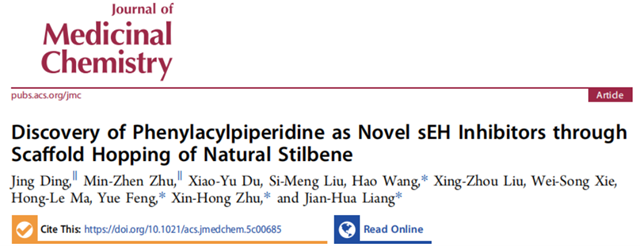

近日,北京理工大學化學與化工學院醫藥分子科學與制劑工程工信部重點實驗室梁建華課題組,以天然產物二苯乙烯為先導物,基于骨架躍遷策略成功優選出一種“新型可溶性環氧水解酶”(sEH)抑制劑DJ-89(化合物77),為臨床需求未滿足的胰腺炎和關節炎的治療帶來新策略,2025年4月14日以“Discovery of Phenylacylpiperidine as Novel sEH Inhibitors through Scaffold Hopping of Natural Stilbene”為題在線發表在國際權威的新藥研發期刊《 Journal of Medicinal Chemistry 》(文章鏈接:https://doi.org/10.1021/acs.jmedchem.5c00685)。該候選藥物的體外sEH酶抑制活性(IC50低至0.51 nM)遠高于現有臨床候選藥物EC5026;并在急性和慢性炎癥動物模型中抗炎鎮痛藥效顯著。在風濕性關節炎模型中DJ-89通過抑制肝臟中sEH酶活性,提高抗炎因子EET水平,有效減輕組織和關節的炎癥癥狀,顯著改善了動物的健康狀況。與現有關節炎臨床藥物治療方法相比,DJ-89具有新的作用靶標和生物途徑,具有優異的臨床安全性,這一研究成果為風濕性關節炎等自身免疫性疾病的治療提供了全新的解決方案。

圖1 二苯乙烯骨架躍遷得到DJ-89治療胰腺炎和關節炎

風濕性關節炎等慢性炎癥性疾病因高致殘率和現有藥物副作用大、療效不穩定等問題,而胰腺炎目前臨床沒有有效藥物,長期面臨治療困境。sEH在炎癥調控中至關重要,它代謝體內的有益的抗炎因子—環氧二十碳三烯酸,促使炎癥發展,成為抗炎藥物研發熱門靶點。不過,此前進入臨床II期試驗的sEH抑制劑,因藥代動力學缺陷或安全性問題折戟,目前沒有任何藥物被批準上市。這一現狀使得開發具有全新化學骨架的藥物變得尤為迫切,也極具重要意義。此前,我們設計了多種骨架的sEH抑制劑( European Journal of Medicinal Chemistry 2024, 266, 116113; European Journal of Medicinal Chemistry 2024, 280.; Journal of Medicinal Chemistry 2024, 67, 18412?18447; Journal of Medicinal Chemistry 2024, 67, 22168-22190.)。此次,我們基于“骨架躍遷”策略,從天然二苯乙烯衍生物出發,設計合成了九種新型骨架化合物,最終篩選出以“苯乙酰哌啶”為核心骨架的DJ-89。該藥物在多項實驗中表現出色:1)超強抑制活性:DJ-89對sEH的抑制活性(IC50 = 0.51 nM)比臨床候選藥EC5026(19 nM)和TPPU(44 nM)高數十倍。2)獨特抗炎機制:通過提升EETs水平并降低其代謝產物DHETs,DJ-89顯著抑制促炎因子(TNF-α、IL-1β)水平,同時增加抗炎因子IL-10水平,這一“雙效調節”機制具有創新性。3)體內顯著療效:在類風濕性關節炎大鼠模型中,DJ-89(10 mg/kg口服)有效減輕關節腫脹和骨侵蝕;在急性胰腺炎模型中,其抑制胰腺組織的炎癥細胞浸潤效果突出,同時血漿IL-6水平下降50%。4)優異的安全性:對hERG和CYP酶影響微弱,大幅降低臨床用藥風險。5)藥代動力學良好:口服生物利用度達8.3%,半衰期1.89小時,且主要富集于sEH表達量高的肝、腎部位,腦部暴露量低,預示其全身抗炎作用顯著且中樞副作用風險小。